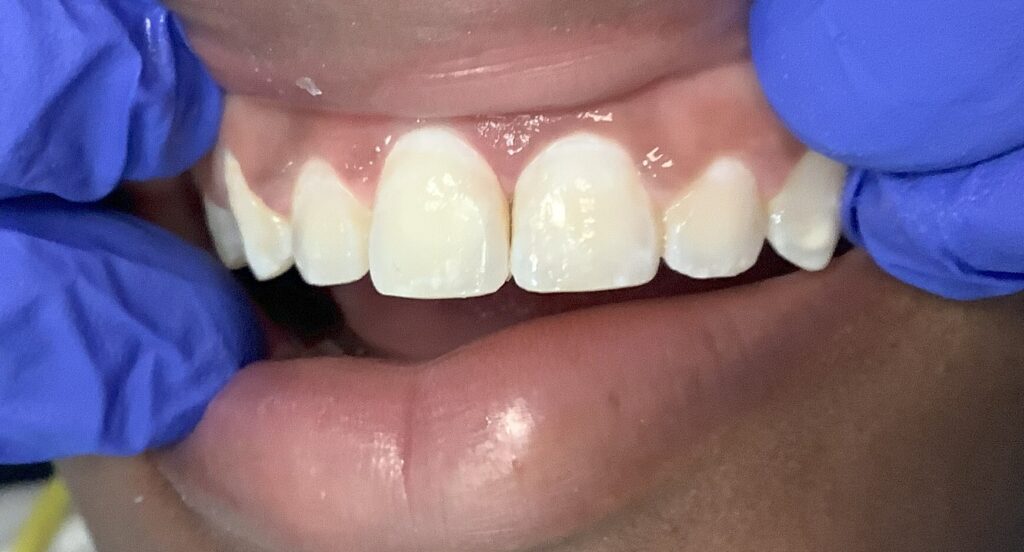

White Spot Removal Results

teeth showing what they looked like before dental work